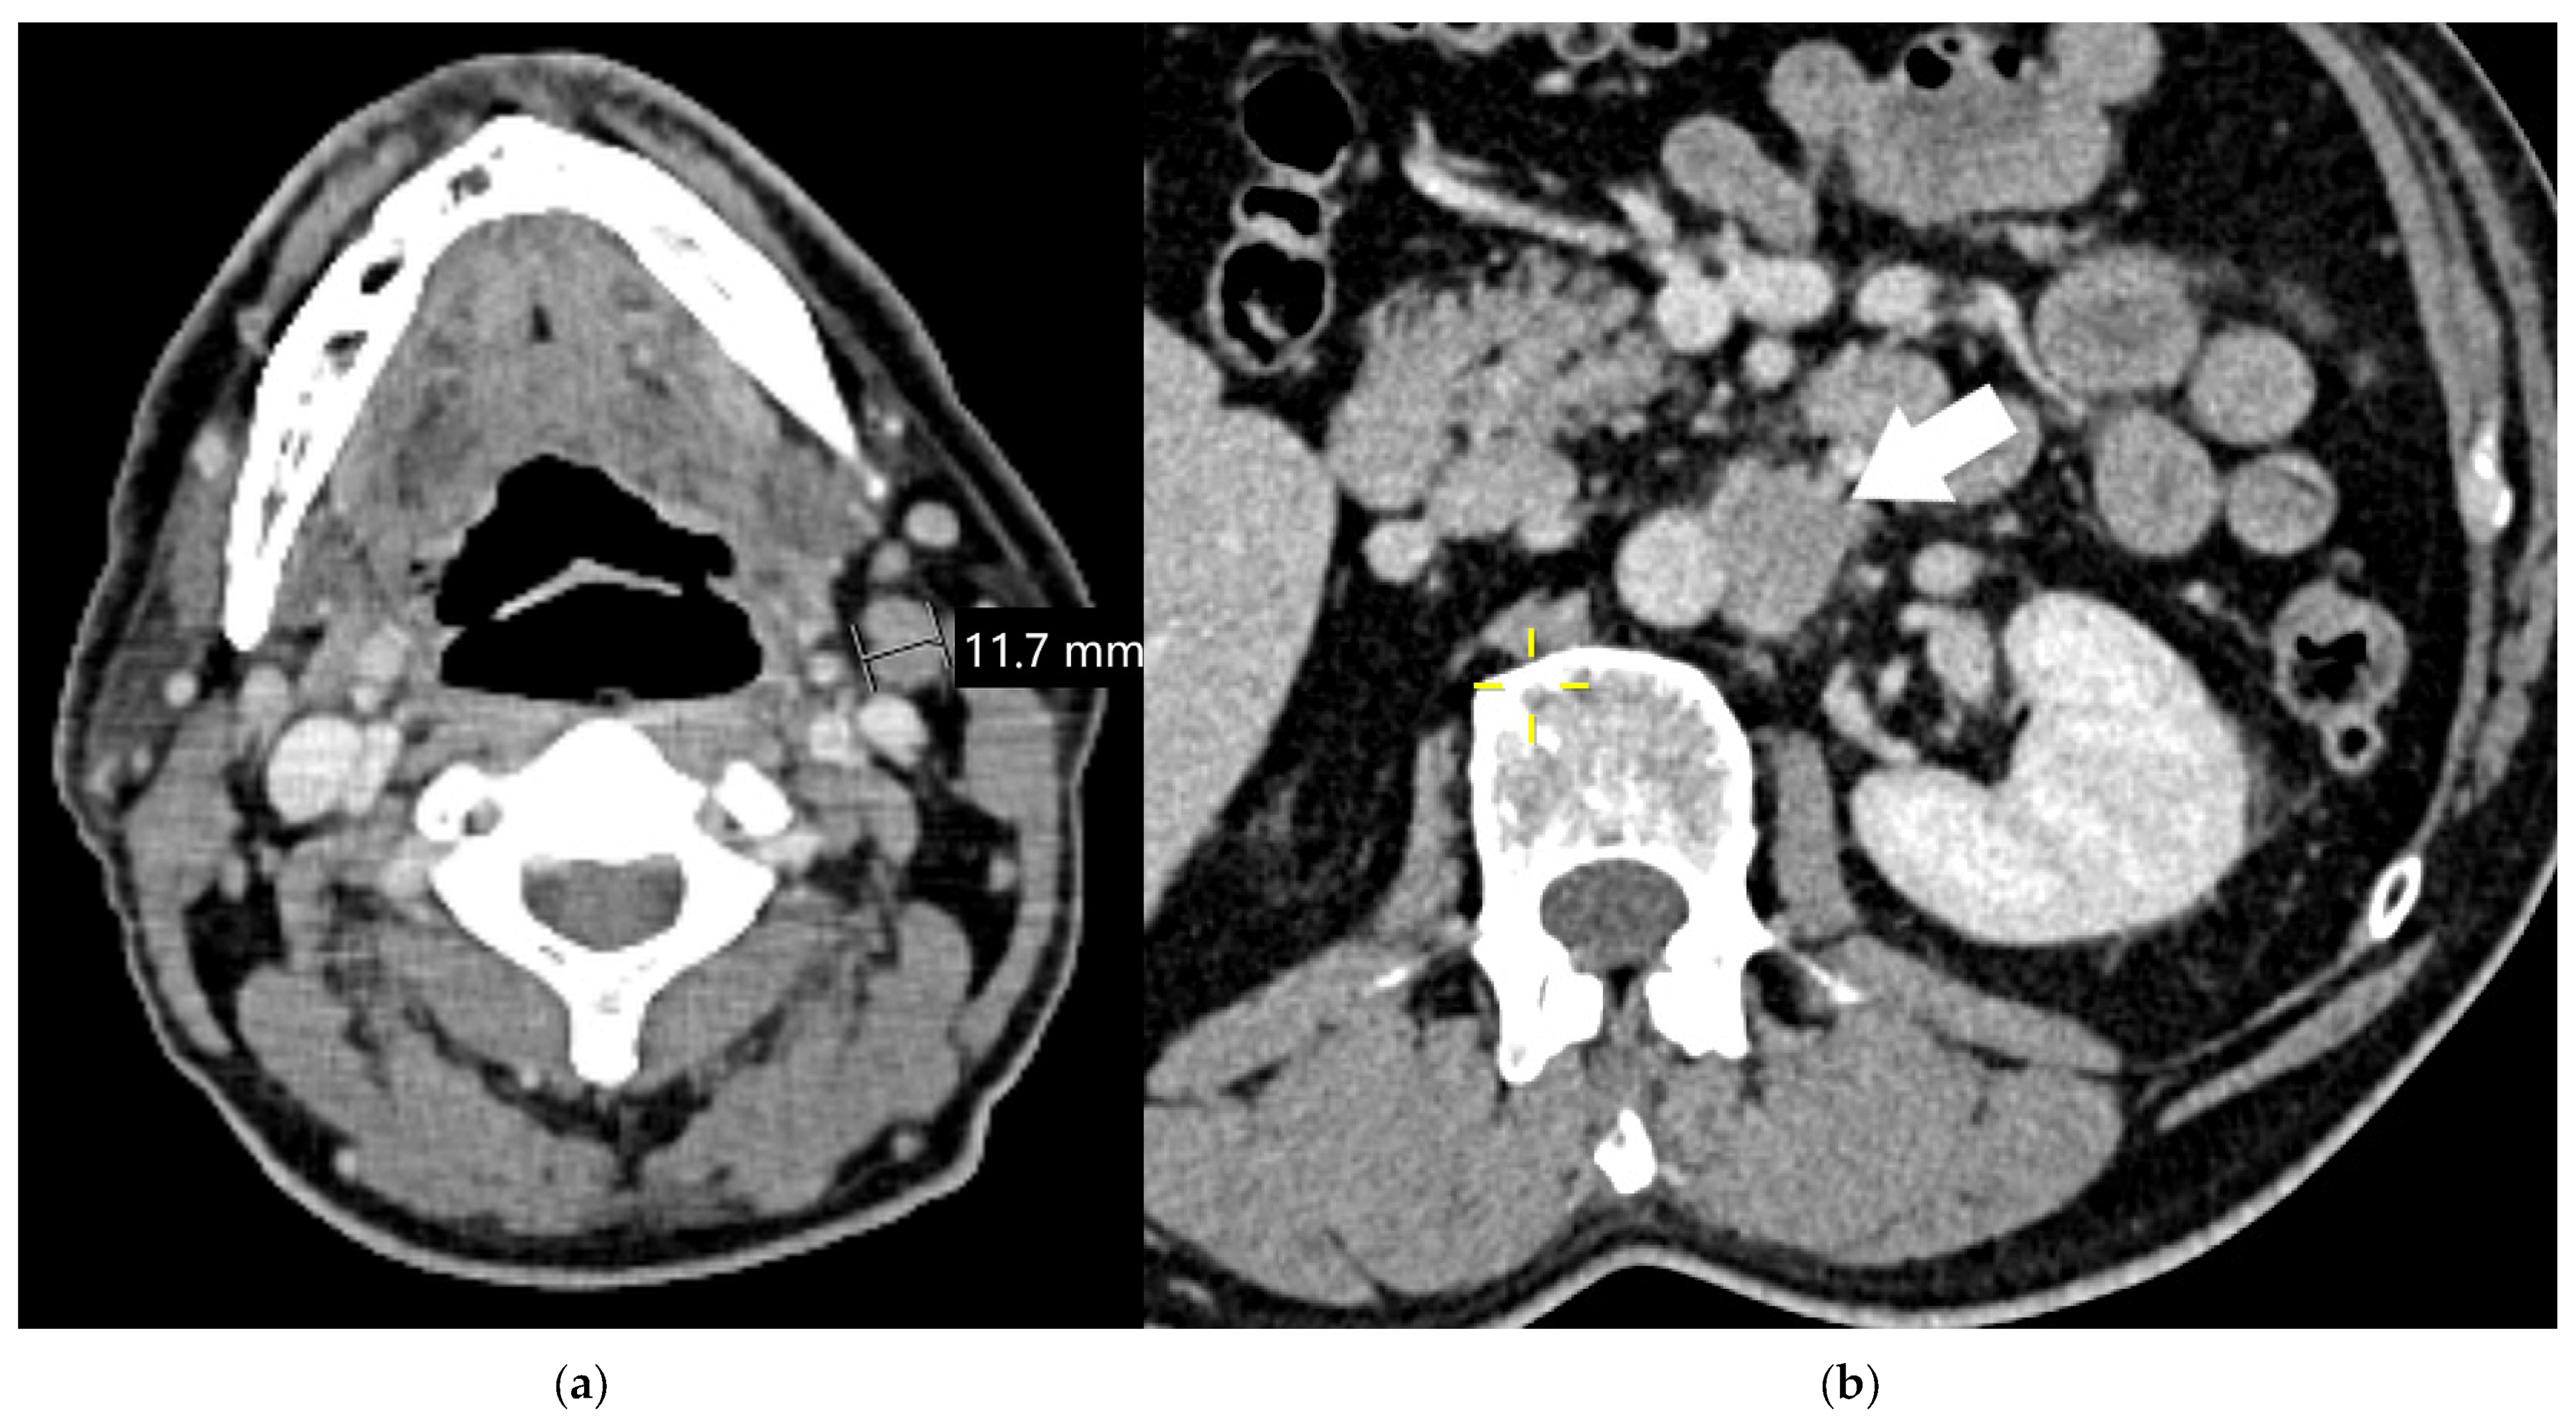

| N3 | Metastasis(es) in contralateral mediastinal, contralateral hilar, ipsilateral or contralateral scalene or supraclavicular lymph node(s) | Metastases to non-regional intrathoracic lymph nodes are considered distant metastases [24,27,76] |